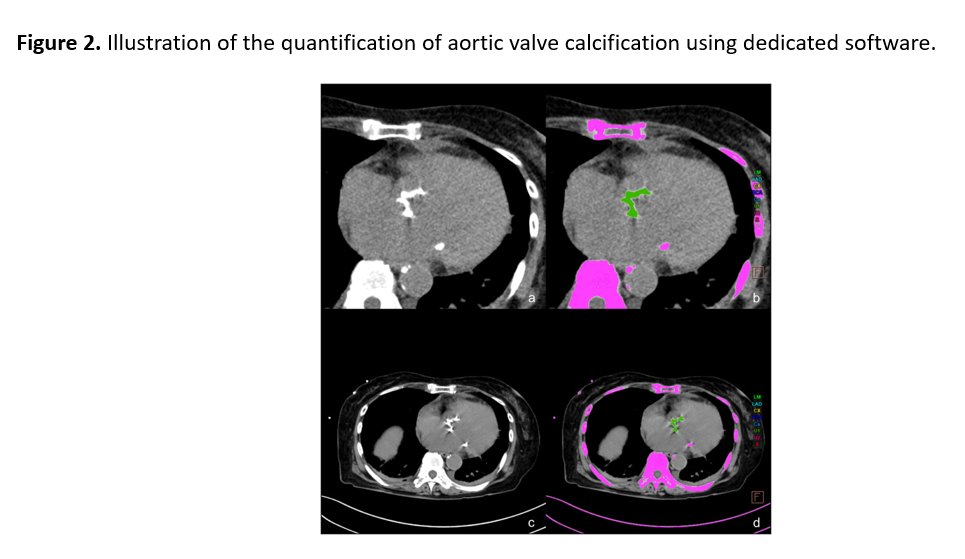

This study from Kisohara et al shows that 5 mm-thick non-contrast body CT aortic-valve Agatston score (AVAS) is a quantitatively feasible tool for evaluating severe aortic stenosis. https://t.co/RfT1PFeXVE.

Not all aortic stenosis looks the same, per this study by Goldfarb et al. CT-based modeling shows that sex-specific aortic valve features improve prediction of stenosis severity beyond calcium score. Anatomical context matters. https://t.co/zQHMBTM6i7